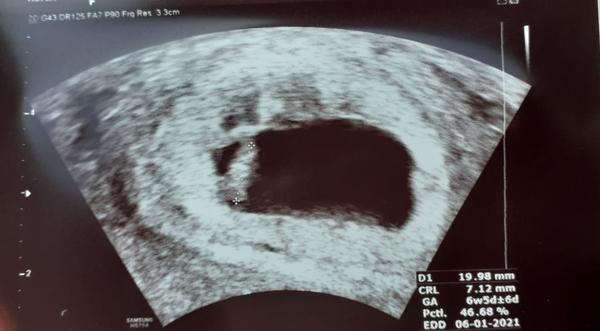

Čus holky, tak já se hlásím po první prohlídce u Dr. a zatím vše v pořádku, potvrzen 7týden, i se srdíčkem. Tak uvidíme dál... 😊